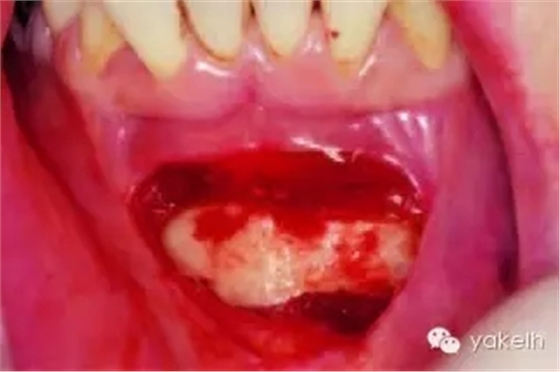

¤¤暴露頦部后,設(shè)計取骨的切口。取骨塊的大小由受區(qū)所需的骨量決定。骨切開處距離根尖以及頦孔最少應(yīng)有5mm。多數(shù)情況下,要保留下頜骨下緣以及舌側(cè)皮質(zhì)骨的完整性。唇側(cè)皮質(zhì)較厚,其內(nèi)側(cè)的松質(zhì)骨通常較致密。可以使用渦輪手機碳合金裂鉆(557號或701號)或者來復(fù)鋸將骨切開(圖13.19)。切透皮質(zhì)骨達(dá)松質(zhì)骨后,用骨鑿將骨塊移除(圖13.20)。用單面鑿沿著骨切開線輕輕敲擊,除了下頜骨下緣,將骨塊從基底部折斷。在中線處時,也可將塊狀骨分割成矩形骨塊,分段獲取。分成兩個骨塊后更容易獲取,因為可以用骨鑿將第二塊骨塊從舌側(cè)撬起。另外,移除塊狀骨后,還可使用骨刮匙、鑿子、咬骨鉗、環(huán)形鉆獲取

一些松質(zhì)骨,但是松質(zhì)骨的量十分有限。在移除塊狀骨后,可以將止血材料如膠原或明膠海綿置于松質(zhì)骨表面。當(dāng)獲取較大的骨塊時,供區(qū)應(yīng)使用骨替代材料如羥基磷灰石,來維持唇側(cè)的外形(圖13.21)。較少或者顆粒狀的骨移植時,可使用環(huán)形鉆、骨收集器、骨挖器來獲取。把骨塊植入受區(qū)后,再將供區(qū)的傷口縫合,這可以縮短取骨與植骨之間的時間。分離前庭溝切口上方的黏膜,以減少水腫和下唇運動所產(chǎn)生的張力。用可吸收縫線分層縫合前庭溝切口(圖13.22)。深層組織使用4-0可吸收線縫合,表層黏膜使用4-0鈷腸線縫合。術(shù)后使用壓力繃帶包扎頦部,以減少水腫、血腫形成及切口裂開(圖13.23)。